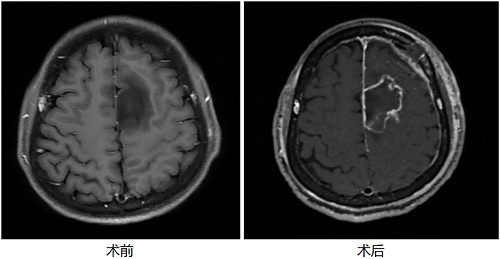

患者为一名29岁的青年男性,因在工作中突发癫痫入院,磁共振检查发现其右侧大脑运动皮层附近胶质瘤,由于肿瘤位置极为接近大脑的运动功能区,常规手术极有可能导致患者运动功能损失,严重影响其生活质量。对于这样一位年轻患者来说,保留运动功能至关重要,如何在保障安全的前提下实现肿瘤的精准切除并切除癫痫灶,成为手术的最大难题。

在本次手术中,朝阳医院神经外科副主任刘长青教授团队采用机器人辅助的术中导航技术,精准锁定肿瘤的边界。同时,结合术中脑电监测技术,通过皮层电极明确运动区的范围以及癫痫放电的范围,团队能够清晰了解肿瘤、癫痫灶与运动皮层的关系,从而确保在切除肿瘤及癫痫灶的过程中不损伤患者的运动功能。术中监测技术极大地提高了手术的安全性,尤其适用于像这位年轻患者一样,对运动功能有高度要求的病例。

借助机器人导航与脑电监测的双重技术保障,刘长青团队在保障精准的前提下,显著缩短了手术时间,并成功实现微创操作。术后,患者运动功能未受影响,恢复迅速,第3天便可下地行走,7天出院。该手术不仅成功切除了肿瘤和癫痫灶,还最大限度地保留了患者的运动能力,为今后的生活质量提供了有力保障。